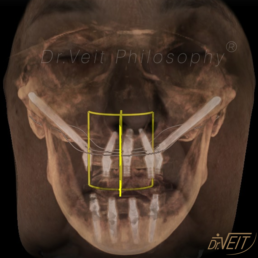

Arte de reabilitar os casos “impossíveis”. Pacientes que buscam a reabilitação oral podem conquistar um belo sorriso com segurança, mais conforto e tranquilidade com o uso do Implante Zigomático. A técnica possui o diferencial de realizar a implantação no osso zigomático e é indicada para casos de perda óssea maxilar avançada.